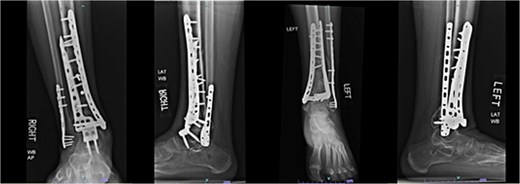

A 38-year-old male with a BMI of 27.5 kg/m2 and a history of alcohol use disorder, paranoid schizophrenia, smoking, and prior bilateral calcaneal fractures treated with ORIF 4 years earlier sustained bilateral pilon fractures after jumping from a third-story window (Fig. 3). He presented to the hospital 5 days after injury.

AP and oblique radiographs of patient 2 obtained after a fall, demonstrating bilateral pilon fractures and retained hardware from prior bilateral calcaneal ORIF.

Despite the patient’s noncompliance, he went on to heal uneventfully for the next 2 years until the patient fell from a height of 15 feet, resulting in a left bicondylar tibial plateau fracture and fracture of the left tibial shaft. These injuries required ORIF of his left tibia. Despite the new injury, the hardware from the pilon fractures was in proper alignment (Fig. 4).

Two-year follow-up AP and lateral radiographs of both ankles in patient 2 showing maintained alignment and hardware position.